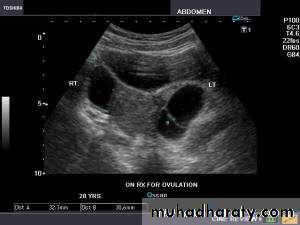

Functional cysts of the ovary - Follicular cysts:

Ultrasonography in Gynaecology

This young female patient underwent sonography for non-specific pain in the lower abdomen. Ultrasound images of the pelvis show bilateral ovarian cysts which show absence of internal nodules, septae or debris. These findings are typical of follicular cysts of the ovaries. Follicular cysts are functional cysts and are enlarged ovarian follicles that have not ruptured (ovulated). They are usually unilateral.